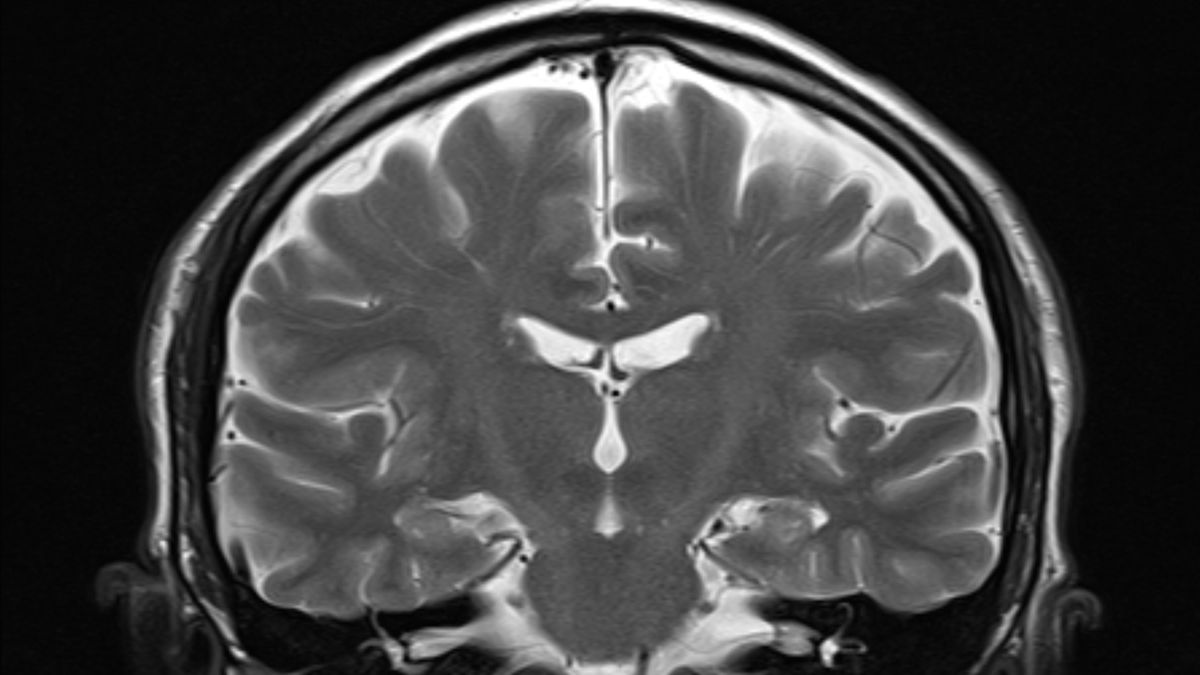

В январе в Центр по контролю и профилактике заболеваний поступили сообщения о том, что дети становятся тяжело больными и умирают от грипп-ассоциированной энцефалопатии или энцефалита (ИАЭ) — спектра неврологических синдромов. Энцефалопатия — это группа заболеваний, вызывающих нарушения функций мозга, в то время как энцефалит приводит к отеку мозга, согласно данным Кливлендской клиники. Симптомы ИАЭ включают судороги, снижение уровня сознания, галлюцинации и изменения личности, длящиеся более 24 часов, говорится в докладе.

В США растет обеспокоенность по поводу осложнений гриппа у детей, особенно связанных с поражением мозга. Согласно отчету CDC, примерно каждая восьмая смерть от гриппа среди детей в этом году связана с грипп-ассоциированной энцефалопатией или энцефалитом (ИАЭ).

Симптомы ИАЭ включают судороги, снижение уровня сознания, галлюцинации и изменения личности. CDC призывает врачей быть бдительными в отношении НАО у детей с гриппом и неврологическими симптомами.